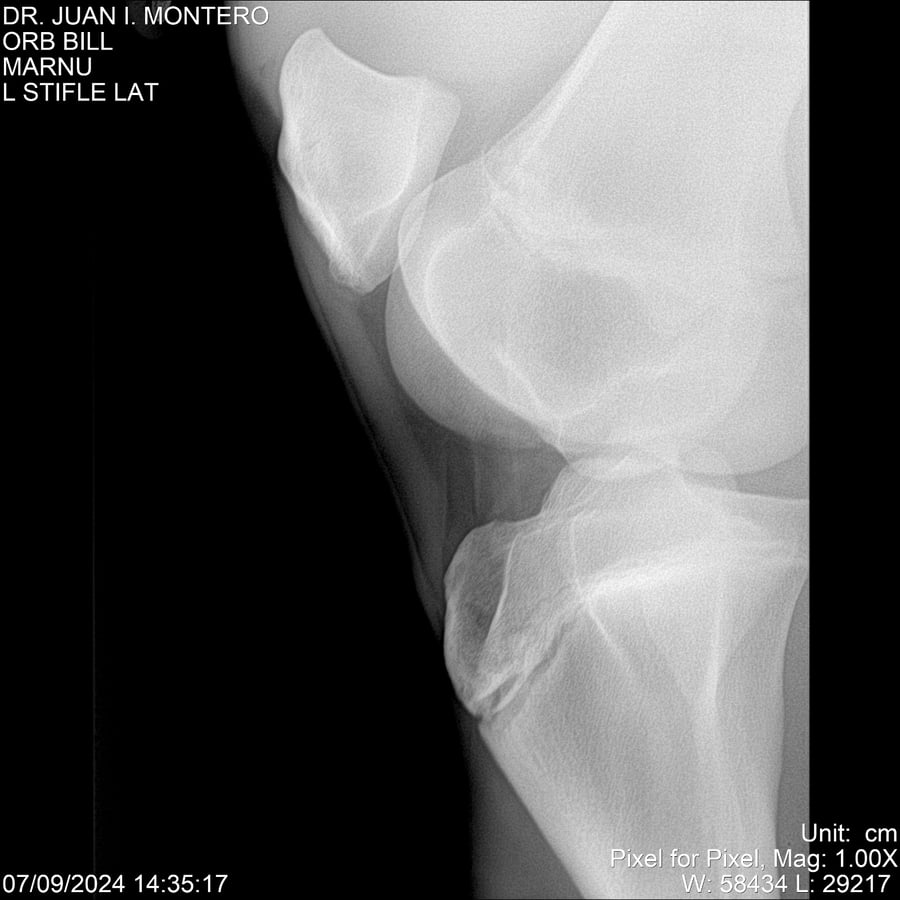

LOTE 7, ORB BILL 🔥 🔥 🔥 Lote Anterior Volver al remate Lote Siguiente Ficha Contacto Montevideo - Ficha del Lote Identificador: #282523 Categoría: Yeguarizos Montevideo - 83 Visualizaciones ClicData Contacto Empresa: Abelenda N. R., Walter Hugo Nombre*: Teléfono* : E-mail* : Mensaje Enviar Registrese gratis Este contenido Exclusivo está disponible sólo para usuarios registrados Ingresar